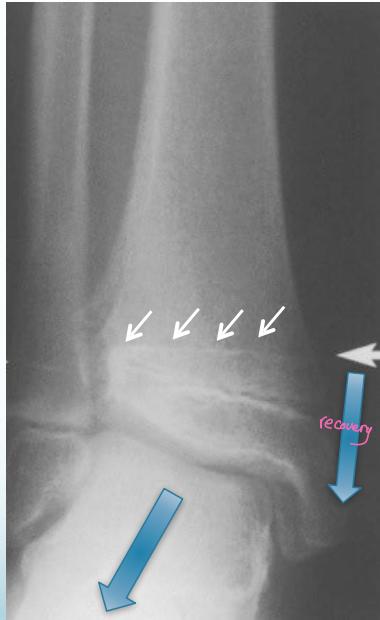

Asymmetrical Physeal Affection

- Seen on x-ray

- One side grows more than the other

- Causing an increasing deformity

- Oblique Park-Harris growth arrest/recovery line (white arrows)